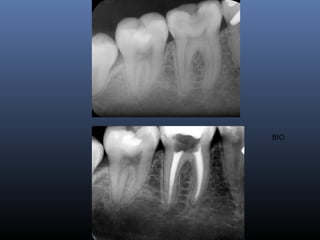

BIO